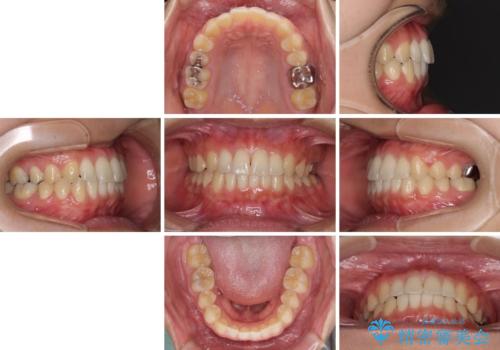

海外勤務中のインビザラインによる矯正治療

- 前歯のクロスバイトを気にして来院され患者様です。

定期的に日本には帰国するものの、日ごろは海外でお仕事をされているとのことで、インビザラインによる治療を希望されました。

トラブルが起こった時に対応ができない、来院を帰国のタイミングに合わせなければならないため治療が長期化するなど困難はありますが、ワイヤー矯正と比べると治療を進めやすいといったメリットがあるので、インビザラインにて矯正治療を行うこととしました。